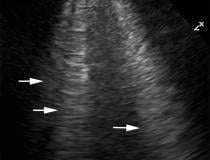

This photo gallery shows the variety of radiological presentations of COVID-19 (SARS-CoV-2) in medical imaging, including computed tomography (CT), radiograph X-rays, ultrasound, echocardiograms and magnetic resonance imaging (MRI). The radiology images show examples of typical COVID pneumonia in the lungs and the numerous complications the virus causes in the body in multiple organs, including the brain, kidneys, heart, abdomen and vascular system.

Ultrasound, especially hand-held ultrasound imaging devices, have become a primary imaging modality for novel coronavirus because of the ease to bag the device and sterilize it after use. CT and mobile X-ray systems are also used as front-line imaging systems for COVID-positive or suspected COVID patients.